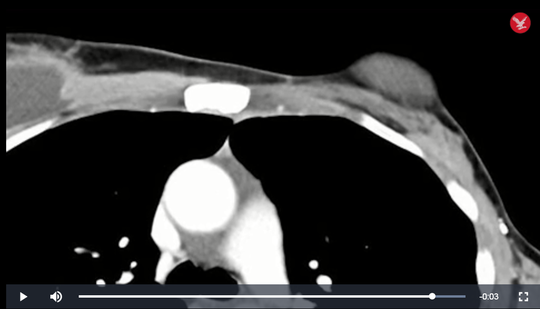

Kết quả là hệ miễn dịch của bà Perkins đã phá hủy rất nhanh chóng khối u chính lẫn các điểm di căn và tự làm bà khỏi bệnh. Hiện nay, sau 2 năm, các bác sĩ đã kiểm tra lại nhiều lần và không phát hiện bất kỳ dấu hiệu nào khác của bệnh ung thư trong cơ thể bà.

Ngực bà Perkins sau điều trị: khối u hoàn toàn biến mất - ảnh cắt từ clip của NCI |